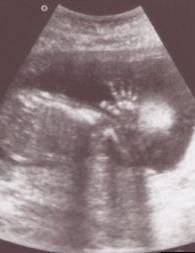

20 haftalık bebek Bebeğinizin cildi sürekli sıvı ortama maruz kaldığı için vernix caseosa adı verilen madde ile koruma altına alındı. 20 cm. ve saçları hızla uzamaya devam ediyor.

Gittikçe büyüyen rahminiz nedeniyle hafif ağrılarınız ve kramplarınız olabilir ama yakında hepsi geçecek.